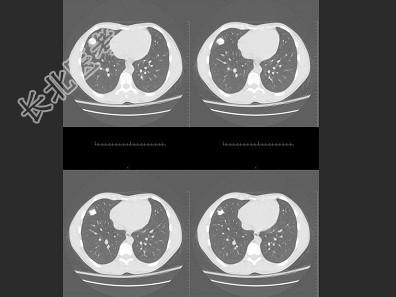

- 单项选择题男,16岁, 咳嗽十余年,结合图像, 最可能的诊断是 ( )

A、胸廓内骨软骨瘤

B、周围型肺癌

C、陈旧性肺结核

D、胸膜粘连

E、以上都不是